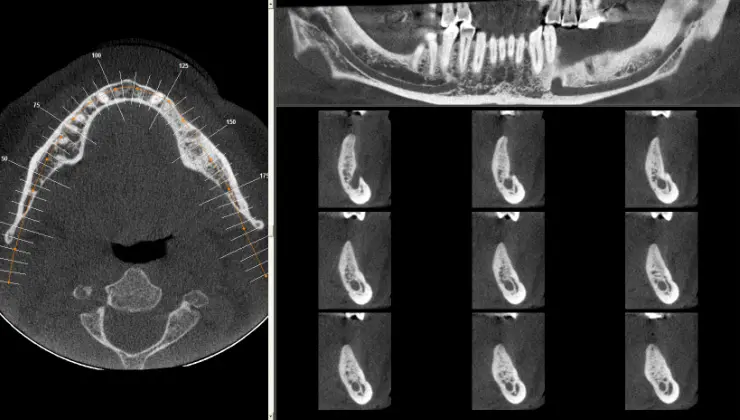

The no cost implant evaluation entails a no cost Panoramic X-ray and an examination to provide you with a treatment plan that is based on your individual needs. Your provider may request that a Cone Beam CT scan (3-dimensional dental scan) be obtained in order to further evaluate and finalize treatment planning. The fee for this scan is $200.00, which will be collected at the time the scan is taken. This scan is not typically covered by most insurance companies; however, we are happy to file a claim if requested, and you will be reimbursed if payment is rendered by your insurance.